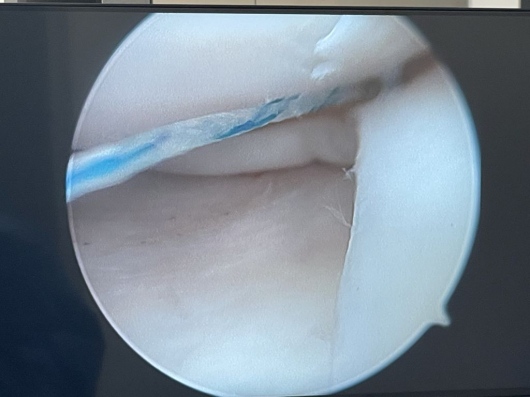

Fotos y videos